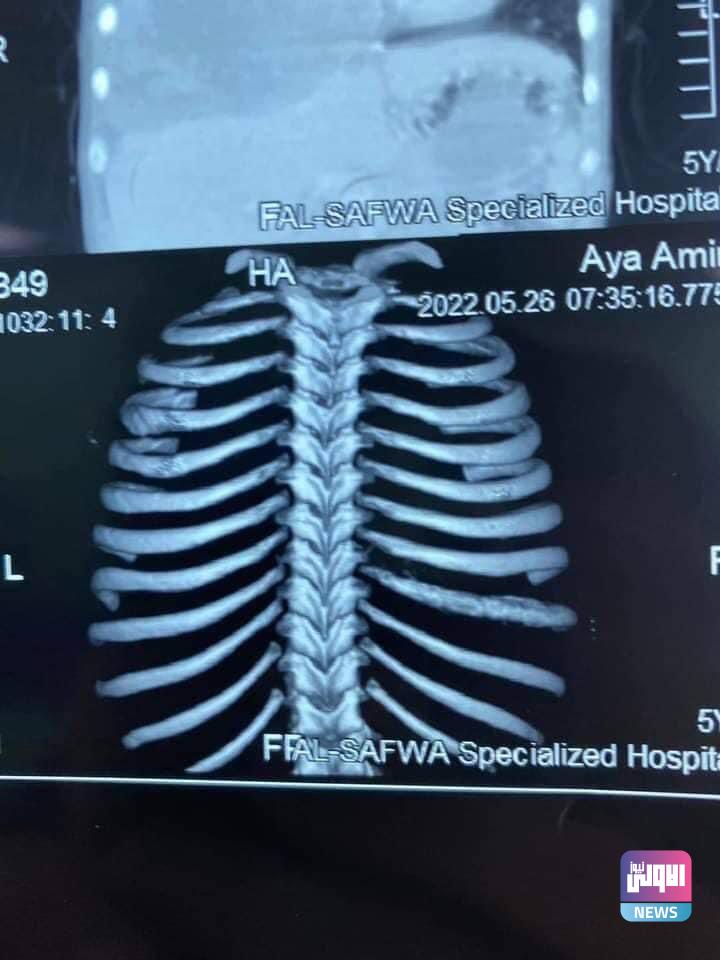

نجح فريق جراحي متخصص بجراحة الصدر والأوعية الدموية في مستشفى الرمادي التعليمي التابع لدائرة صحة الأنبار يإجراء عملية استئصال ورم من طفلة مريضة بعمر 6 سنوات

وذكر رئيس الفريق الجراحي الدكتور بشار برجس اختصاص جراحة الصدر والاوعية الدموية ان الطفلة كانت تعاني من وجود ورم في التجويف الصدري الملتصق بشخاف القلب والرئة والحجاب الحاجز .

مؤكدآ ان عملية استئصال الورم بالكامل وتكللت بالنجاح التام والطفلة بصحة جيدة بجهود الفريق الطبي والجراحي والتمريضي الساند.